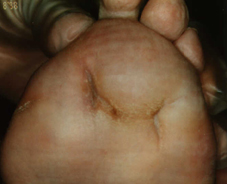

Perforating ulcer of 18x16mm with inserted Septopal chain.

Removal of the Septopal chain with the forceps, under it the structur of the metatarsal bone is visible. Assuming that this is a sequestrum, careful attempt of removal with Luer´s bone nibblers. But the assumed sequestrum is the osteomyelitic mutated part of the 2® metatarsal bone. After irrigation of the wound with Lavasept a 2 cm deep cavity remains, that is treated with sterile LIGASANO® white and irrigation with Oxoferin. Closure within four weeks.